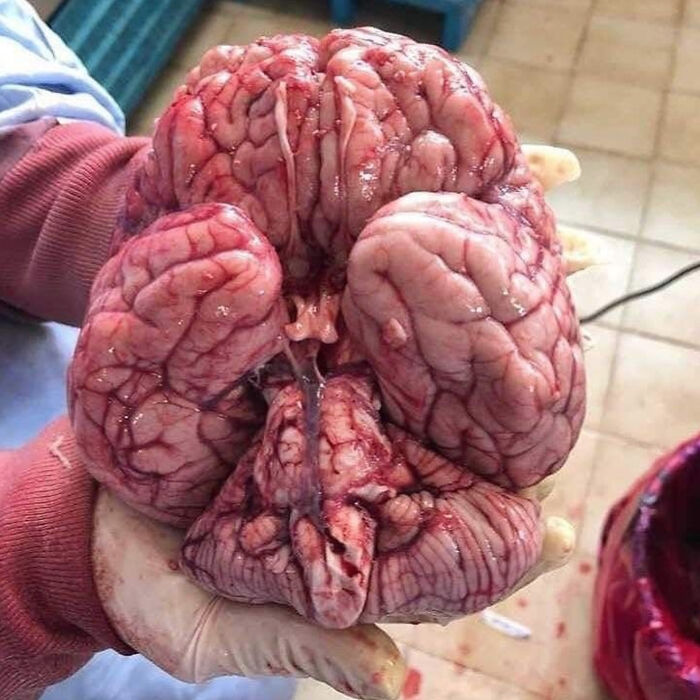

The Base Of The Brain Is A Masterpiece On Its Own!